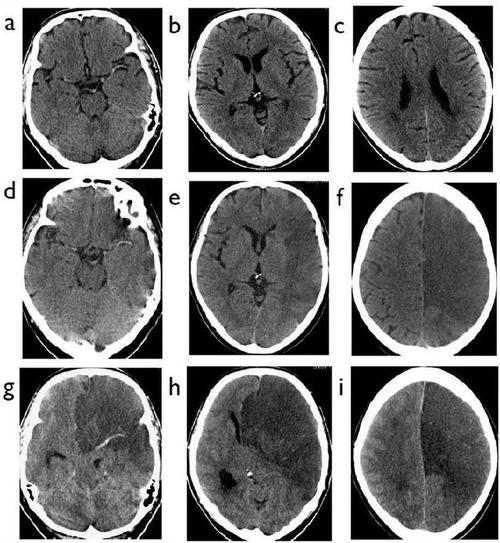

6 个病例学会「脑梗死」的 4 大 ct 征象

没有mri,超早期如何利用ct诊断脑梗死

掌握5个征象,ct也能诊断超早期脑梗死

超急性期大面积脑梗死 ct 平扫表现

脑梗死患者的头部ct,你真的会看吗?丨实战读片